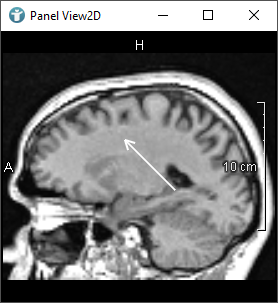

The following images show editors available in MeVisLab for drawing CSOs:

The SoCSOIsoEditor and SoCSOLiveWireEditor are special, because they are using an algorithm to detect edges themselves.

- The

SoCSOIsoEditorgenerates isocontours interactively. - The

SoCSOLiveWireEditorrenders and semi-interactively generates CSOs based on the LiveWire algorithm.